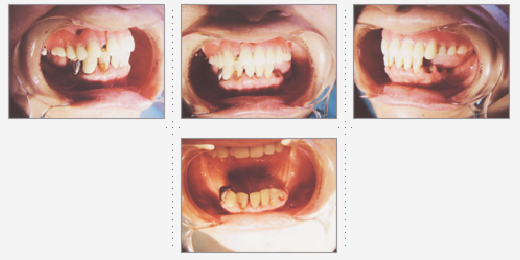

会社員 49才 男性

奥様から、ご主人の上顎前突(出っ歯)を直してほしいとご依頼がありました。

期間役1ヶ月で、出っ歯が改善されると、やさしい印象になりました。